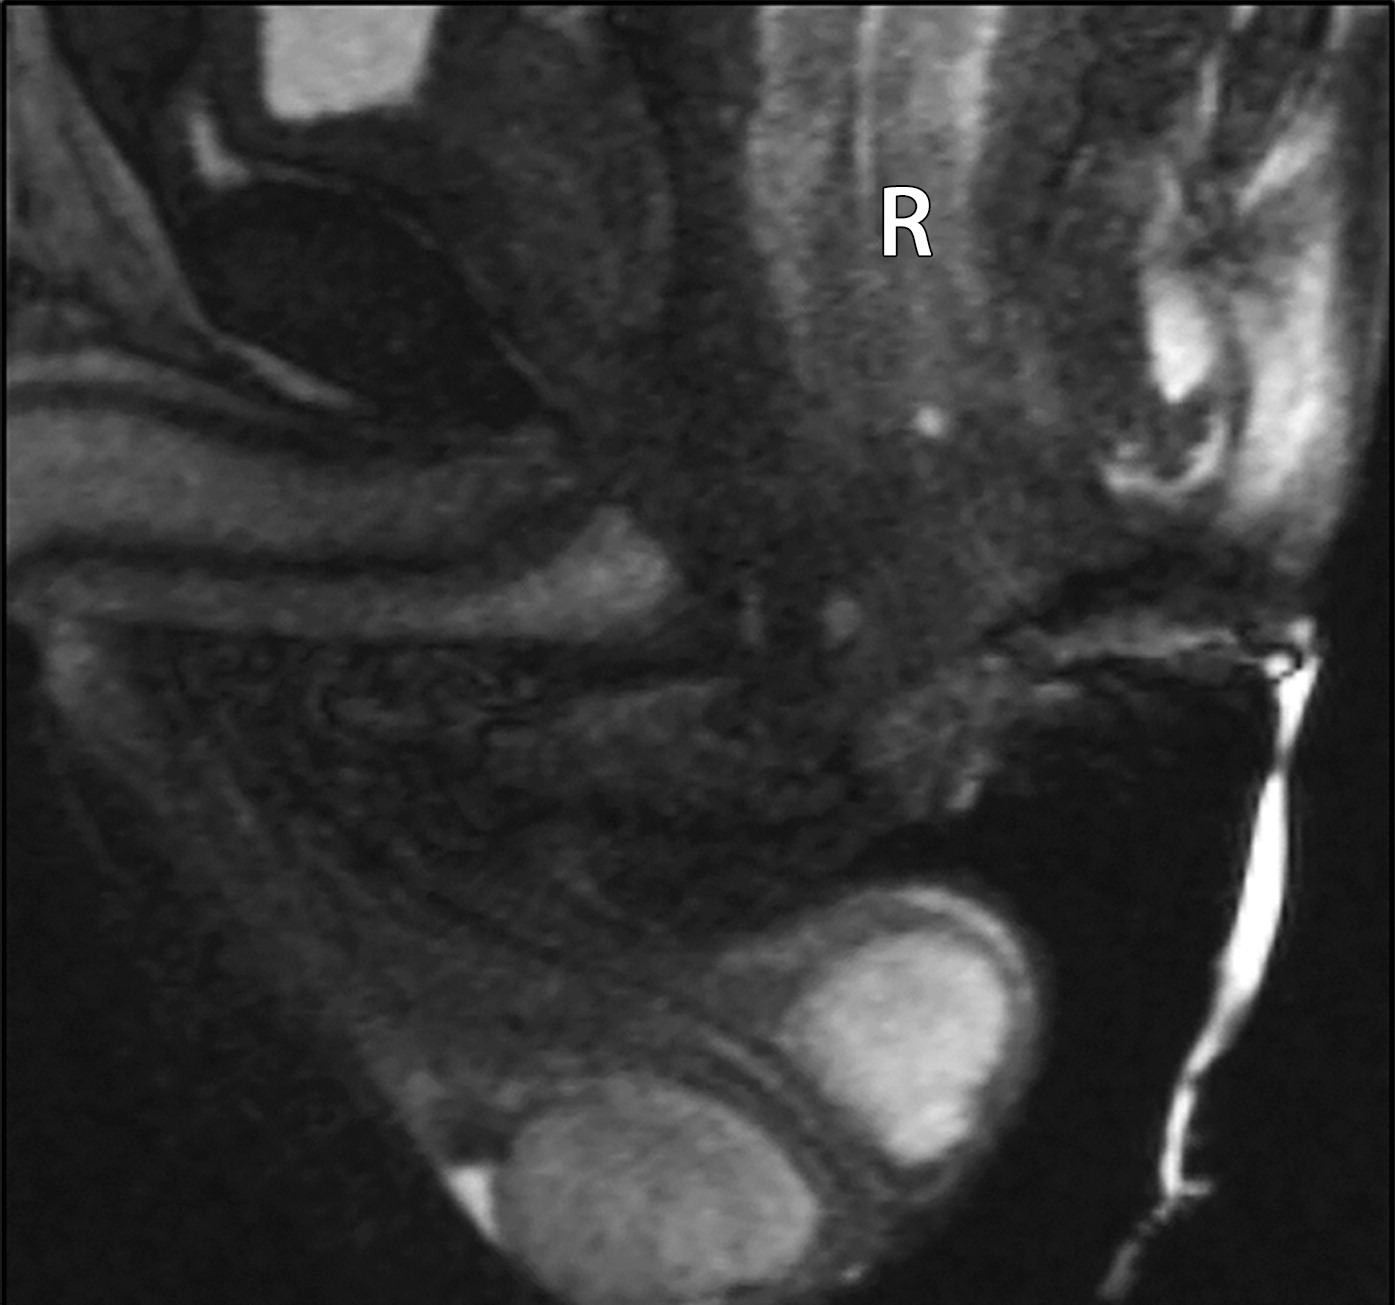

5b37c973dc3130b025d5647c71540da5.jpeg279c20ad5aa41e2c495e2183e2cf526d.jpeg

直肠脱垂。

(a图)为静息态,(b图)为增加腹压态。可见直肠(白色字母R)及轴位的腹膜脂肪(黑色字母F)在增加腹压时全层脱垂。